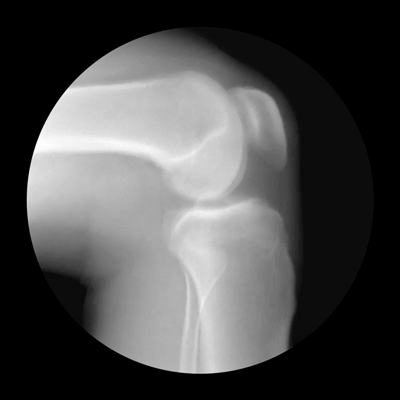

第八:骨骼系统

包括骨、关节、骨骼组成。原因:以上各系统及泌尿系统受到损伤,骨骼系统平衡能力降低,疾病真正侵袭入人体深层骨组织,该系统开始出现骨骼细胞增生速度加快、钙流失过度、骨关节胶原蛋白受损,造成骨质疏松、增生等。疾病列举:骨质疏松、缺钙、骨质增生、腰椎增生、关节炎、骨膜炎等。